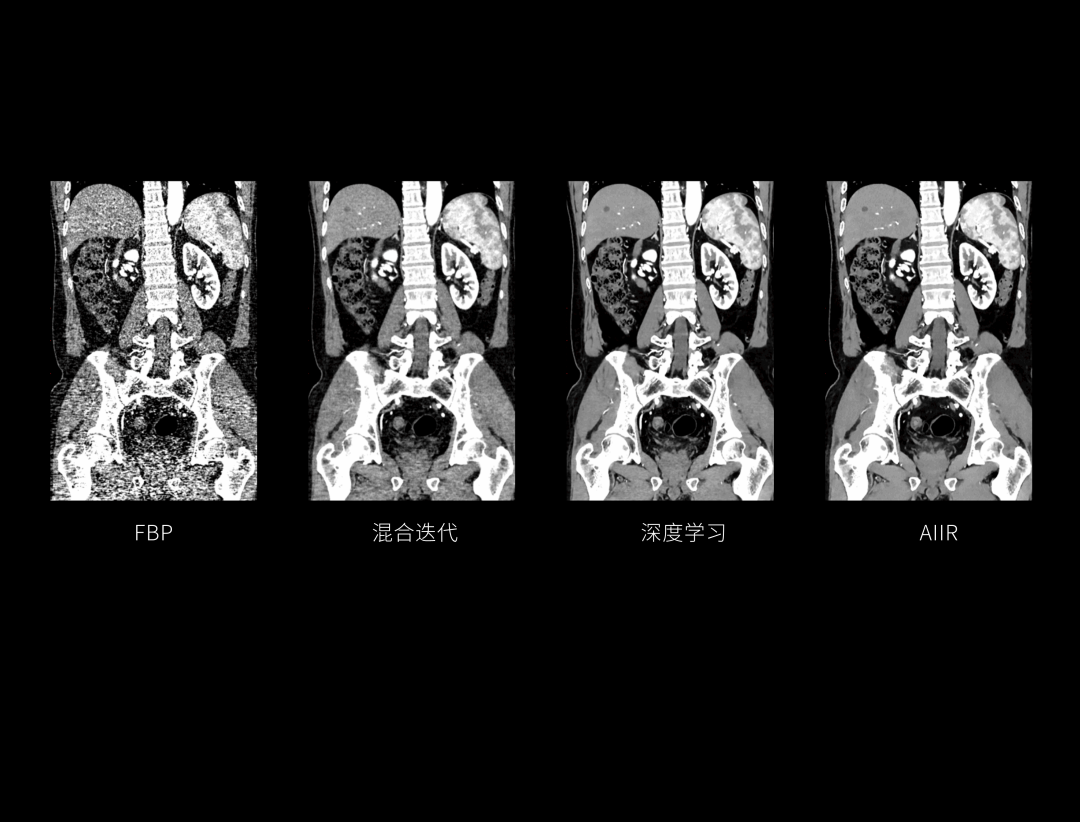

AIIR图像重建提升结果图像可解释性与算法鲁棒性,获得低剂量下的高清成像,超越传统,引领CT成像新标准